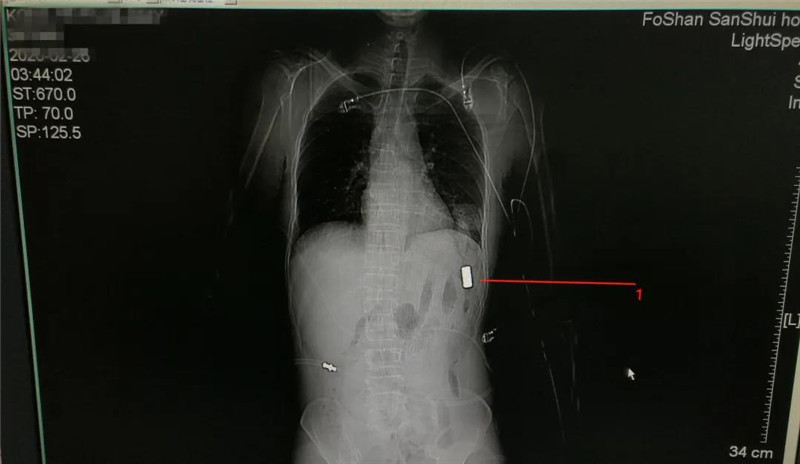

400度高温金属模具突然爆炸击穿男子肺部,多科专家联手成功救治

“工作时400多度高温模具不慎爆炸,男子被疑似金属击穿肺部。CT提示左前胸胸腔内(左膈肌前缘)有金属异物存留、左侧第6肋骨骨折,合并血胸。”2月26日,受伤男子被送至三水区人民医院急诊科,普外一区心胸外科和普外二区手术团队联手用4小时手术完...